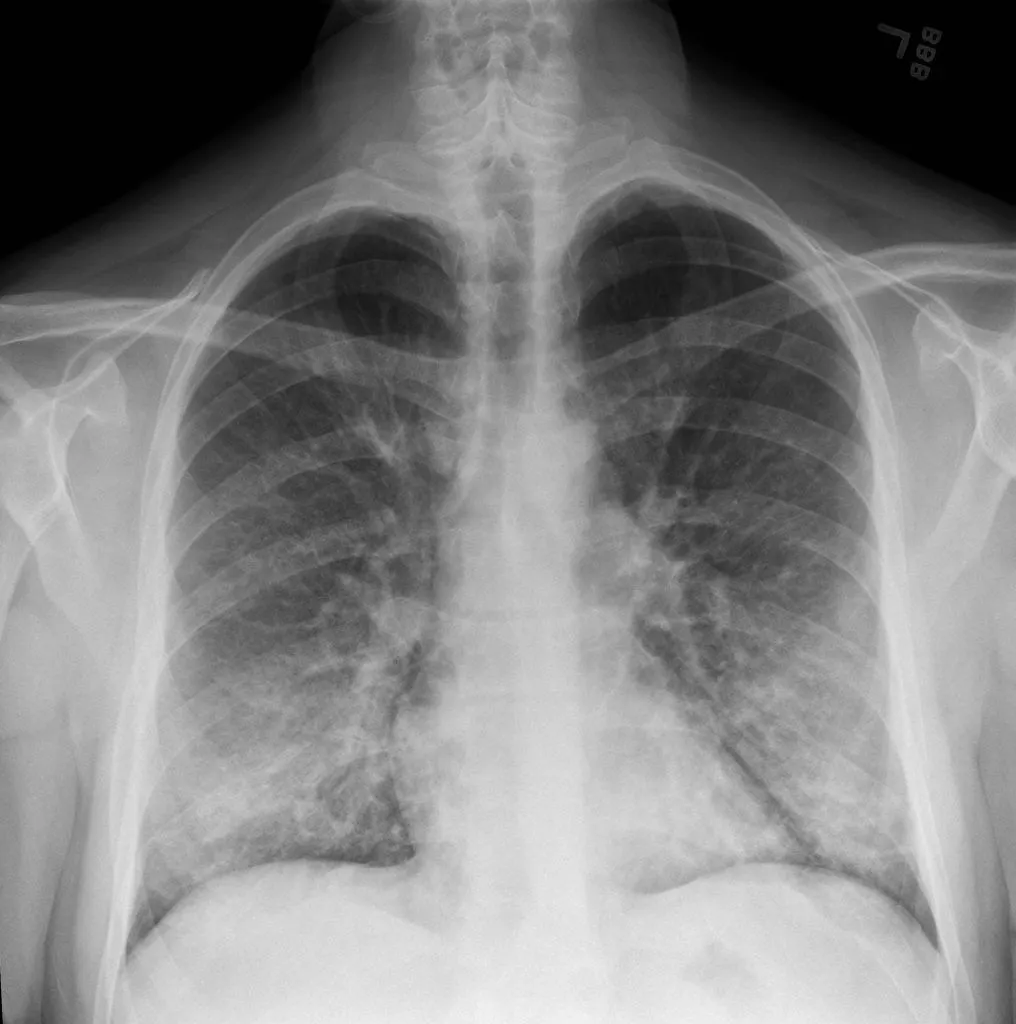

Fuente: Radiografía y scanner de pacientes con daño asociado al consumo de cigarrillo electrónico The New York times

Los casos se han presentado con aparición gradual de síntomas y siempre con el antecedente de haber usado cigarrillos electrónicos, ya sea con nicotina o con THC (constituyente del cannabis) (2). De estos últimos, se ha identificado que la mayoría contenía vitamina E acetato. Los síntomas reportados son: dificultad respiratoria y dolor en el pecho. Algunas personas también han informado padecer síntomas gastrointestinales, como vómitos y diarrea. También han registrado otros síntomas como fiebre, taquicardia y fatiga.

Este síndrome respiratorio se ha dado en un contexto no infeccioso, por lo que los especialistas están investigando cuál es el rol de los cigarrillos electrónicos en los casos.